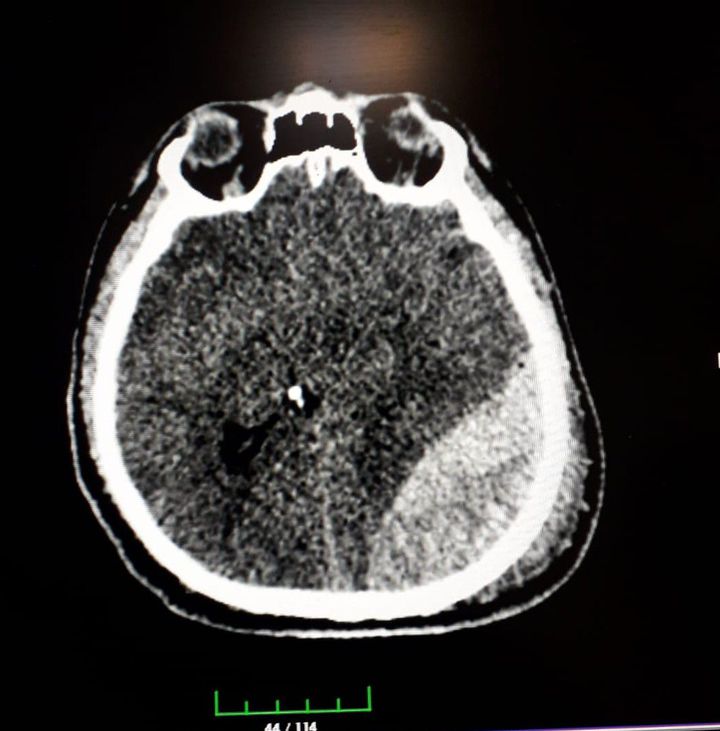

Epidural hematoma

32 years-old man patients. Epidural hematoma due to motorcycle accident.